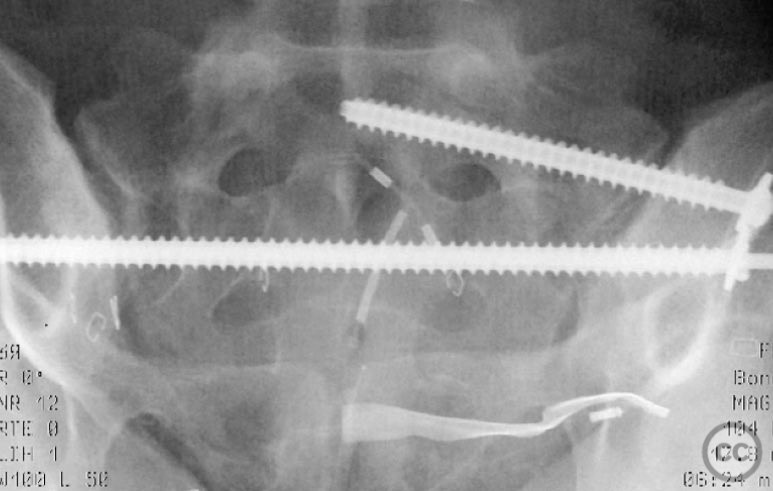

Clinical Details

Clinical and radiological findings:  A 26-year-old female sustained a closed pelvic ring injury following a motor vehicle accident. She was hemodynamically stable, neurologically intact, and had no other associated injuries. Skin integrity was preserved. Initial management included pelvic binder application and 10 pounds of distal femoral skeletal traction. Portable AP pelvic radiograph demonstrated a left-sided sacral fracture with associated ipsilateral iliac wing and pubic ramus fractures, consistent with an AO/OTA 61-B2 (lateral compression type II) injury pattern.

Anatomical surgical approach:  The left sacral fracture was addressed first via percutaneous placement of iliosacral screws under fluoroscopic guidance. An anterior approach to the iliac wing was performed via a longitudinal incision along the crista iliaca, subperiosteal dissection to expose the fractura alae ossis ilii, followed by debridement, reduction, and temporary clamping. Definitive fixation was achieved with two 7mm diameter cannulated fully threaded medullary screws placed across the iliac crest and pelvic brim into the corpus ossis ilii. The left ramus ossis pubis fracture and overall cingulum pelvicum were assessed intraoperatively with fluoroscopy for residual instability.

Operative remarks:

Intraoperatively, minimal residual deformity of the left hemipelvis was noted after traction and positioning. The sacral fracture was stabilized first with iliosacral screws. The anterior iliac exposure allowed for direct visualization, cleaning, reduction, and clamping of the iliac wing fracture prior to screw fixation. After fixation, intraoperative fluoroscopic stress examination demonstrated stability of the left pubic ramus fracture and overall pelvic ring, obviating the need for further anterior fixation.

Orthopaedic implants used:   Two 7mm diameter cannulated fully threaded medullary screws (iliac crest and pelvic brim), percutaneous iliosacral screw(s).